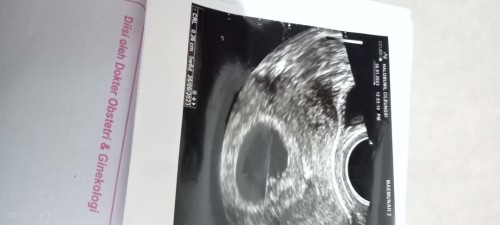

Jadi aku nikah 25 Desember, hpht aku 19 desember 2022, dan tgl 30 Januari 2023 aku USG UK kehamilan 5w6d sudah ada djj nya, dan tgl 23 feb aku USG lagi, seharusnya 9 week kan? Tapi kata dr nya sudah 11 week, apa mungkin dr salah ngukur panjang janin? Karena setau aku, kalo nitikin ga sesuai itu jadi beda usia kehamilannya, mungkin bunda disini ada yg mengerti🙏 soalnya mertua aku bilang nikah aja baru 2 bulan, kok hamil udh mau 3 bulan #seriusnanya #bantusharing

Bun aku nikah 25 Desember 2022, menurut hpht hpl aku 26 September 2023, tgl 30 jan 2023 aku USG sudah ada janinnya UK 5 week6 day terus hari ini USG UK sudah 11 week 2 day dan hpl jadi 12 September 2023, mohon penjelasannya Bun aku ga ngerti, dokter aku tanyain cuma bilang janinnya tinggi terus kek buru2 dia #ingintahu #seriusnanya #bantusharing